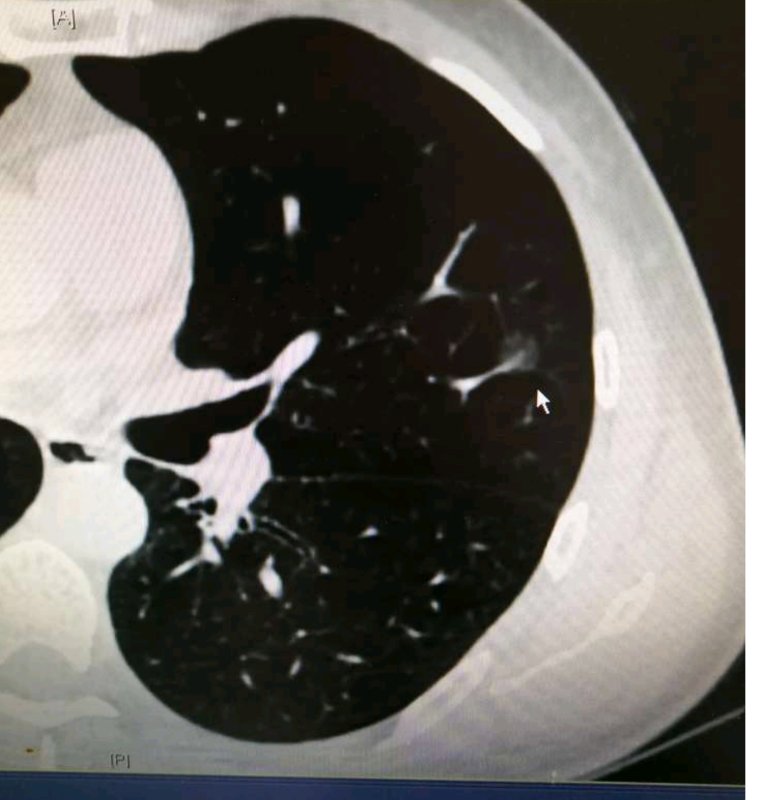

2010年时,吴先生在一次偶然的体检中发现自己左肺上有两个磨玻璃结节,去陆军军医大学新桥医院胸外科复诊时碰到了姚珂教授团队,姚教授仔细看过检查结果后发现他的两个结节位置都比较深,可能一般的楔形手术无法将结节切除干净,只能进行肺叶手术,考虑到结节比较小且表现都十分良好,恶变的概率很小,便建议他先随访一段时间。“那个时候我虽然很害怕,但是姚教授仔细帮我分析了,这两个结节如果要做手术的话就得做肺叶手术,一个人总的就只有5片肺叶,切掉一整片对后面的生活多多少少总会有些影响,他认为我还年轻并且结节恶变的概率几乎为零,所以让我先随访,如果结节有变化了再做手术也不迟。我想了很久,觉得姚教授说的有道理,毕竟那个时候我才三十多岁,家里很多苦活累活都需要我,所以我就听大夫的话,根据医嘱进行随访,谁知道竟然随访了九年,这对我的身体和精神来说都是一场持久战,还好今年终于把这个麻烦解决掉了。”说到这个,吴先生不禁满面笑容。

“这个患者,我印象很深,每年见一次都算是老熟人了”,一说到吴先生,姚教授立马就有印象:“在临床工作中我们碰到过很多磨玻璃结节患者,他们大多分为三类,第一类患者对磨玻璃结节一知半解,知道这种结节恶变概率高,发现结节后心理压力太大,吃不香睡不着,甚至会影响正常生活,这类患者不管结节的大小或具体表现如何都会强烈要求进行手术,不把结节切掉基本没法正常生活;第二类患者则完全相反,听到医生说磨玻璃结节惰性生长,并且结节表现良好建议随访时大多不会太放在心上,最开始一两年还能定期来医院随访检查,如果没啥变化则会将其抛诸脑后,等到后面出现症状再就诊时结节多已发展到中晚期。这两种患者在临床工作中是最常见的,但二者的心态都太极端,均不可取。吴先生这种情况则属于第三类患者,依从性好,医生解释后能放下大部分的心理负担,但又能谨记医嘱坚持随访,结节一旦发生变化就能及时手术,所以结节就算有所发展也多在肺癌早期,这类患者的预后一般都比较好。吴先生的两个结节都是IA期腺泡型肺腺癌,做完手术都不用再做辅助放化疗,治愈率非常高。”